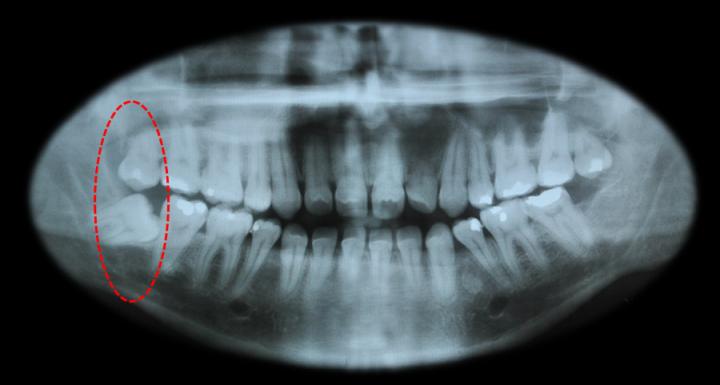

Now the title of this post reads Mesioangular impaction, well it refers to a wisdom tooth that is angled towards the front of the mouth.. I thought I was unique until I found that am not alone 😉 over 44% of the folks face the same problem. For all you folks who think why the F*#% in the world would anyone write about a tooth extraction, “ Go !!! get one removed :-@ “. This post is all about preparing for the tooth extraction and what need to be done aft.